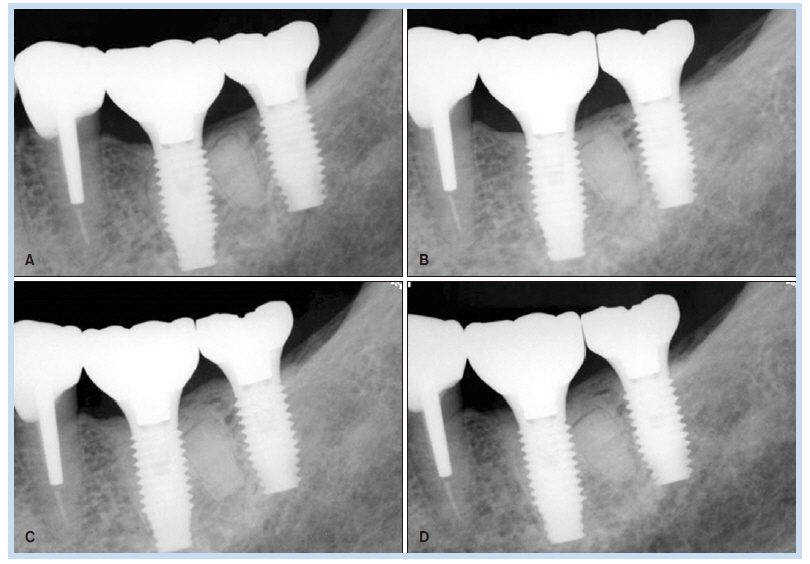

69세 여자 환자가 하악 좌측 제1, 2대구치 상실로 인한 저작의 어려움을 주소로 내원하였다. 하악 좌측 제1, 2대 구치는 6년 전 발치된 상태였고, 하악 좌측 제1대구치의 치근이 잔존해 있는 상태였다(Fig. 1). 내원하기 1개월 전 하악 좌측 제1대구치 부위에 통증이 있었다고 하였지만, 내원 시에는 통증이 없는 상태였다. 심장센터에서 부정맥 치료 중인 환자로 하악 좌측 제1대구치 잔존 치근을 발거하고 하악 좌측 제1, 2대구치 부위에 임플란트를 식립하기로 계획하였다. #46 잔존 치근을 발거하고 치조정 절개를 가하여 피판을 거상한 후 임플란트 drilling을 시행하였다. 그 후 하악 제1대구치에 직경 4.8 mm, 길이 1.5 mm의 임플란트, 하악 제2대구치에 직경 4.8 mm, 길이 10 mm의 임플란트를 일회법으로 식립(Osstem SS II; Osstem Implant, Seoul, Korea)하였다. 치유 지대주(healing abutment)를 연결 후 피판을 재위치시키고 4-0 Vicryl (Johnson & Johnson, New Brunswick, NJ, USA)로 봉합하였다. 임플란트 식립 1주일 후 봉합사를 제거하고 파노라마 방사선 사진과 치근단 방사선 사진을 촬영하였다. 이때 #36 부위에 원심 치근으로 추정되는 방사선 불투과상이 관찰되었으나 감염 등 특별한 증상이 없었고 잔존 치근을 무리하게 제거한다면 그로 인한 골소실 및 임플란트 골유착에 오히려 방해가 될 수 있다고 판단하여 잔존시킨 상태에서 정기적 관찰을 결정하였다(Fig. 2, 3). 임플란트 식립 2개월 후 최종 보철물이 장착되었으며 임플란트 식립 후 115개월간의 치근단 방사선 사진을 통한 경과 관찰 시 안정적으로 임플란트가 유지되고 있음을 관찰할 수 있었다(Fig. 4, 5).

Fig. 4. Follow-up periapical radiograph. (A) Periapical radiograph 4 months after implant placement. (B) Periapical radiograph 12 months after implant placement. (C) Periapical radiograph 67 months after implant placement. (D) Periapical radiograph 87 months after implant placement.